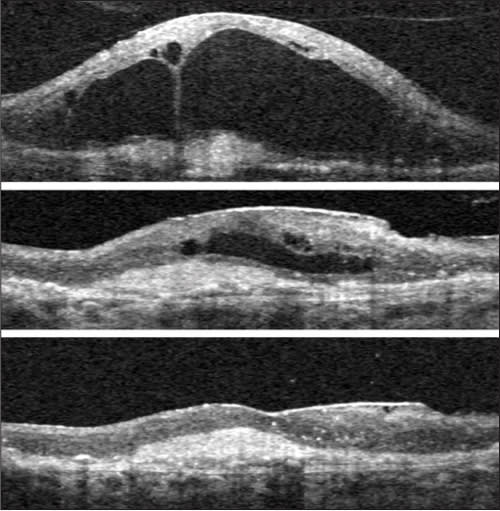

We did find a number of eyes in which removal of vitreomacular traction did appear to flatten the retina, and this was associated with vision improvement. (Figure 3). Unfortunately, it also appears that such surgery is not associated with permanent drying of the retina; rather, it is still necessary to maintain regular monthly anti-VEGF treatment. One concern of our group is that the half-life of anti-VEGF drugs in vitrectomized eyes is shorter than in nonvitrectomized eyes and that anti-VEGF treatment in vitrectomized eyes may be suboptimal, even if higher doses are used. Of course, such concerns would be reduced if a long-acting delivery devices or drug formulation is developed.

Figure 3. Exudative age-related macular degeneration with vitreomacular traction, surgical outcome (patient #4). Vertical spectral-domain optical coherence tomography scans through the center of the macula are shown. Top: Baseline scan shows vitreous adherent to the apex of large cavities within edematous retina, and an underlying choroidal neovascularization complex; this fluid persisted despite eight previous monthly injections of intravitreal bevacizumab. Middle: Image shows center of macula one month after vitrectomy with removal of the attached hyaloid membrane. Fluid is reabsorbing (note: the scale is adjusted to facilitate direct comparison with the other scans). Bottom (same magnification as top) six months follow-up: complete reabsorption of intra- and subretinal fluid. Monthly bevacizumab treatment was continued after surgery. Vision improved by one line, from 20/400 to 20/320.